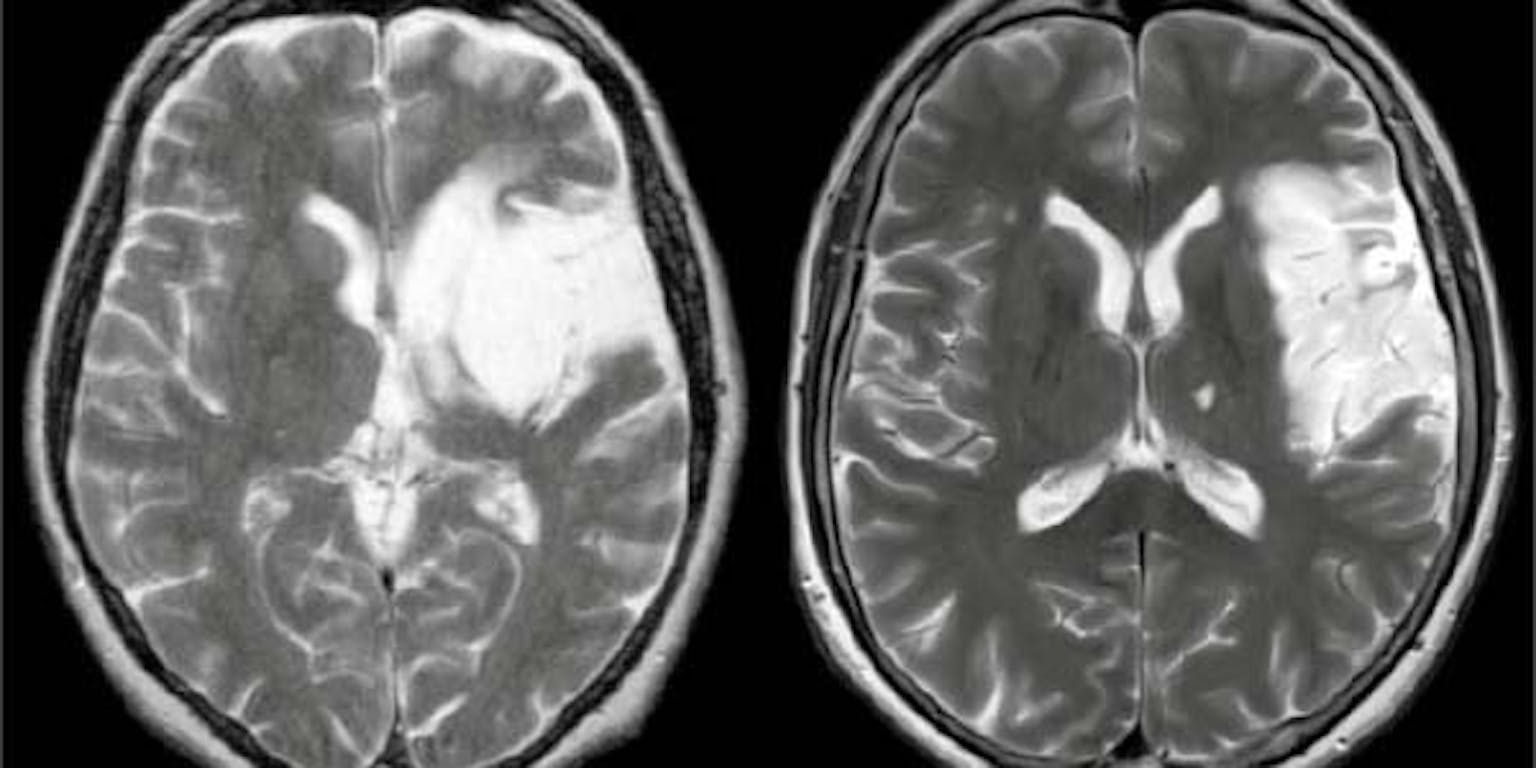

Hersenbeschadiging na beroerte. Kan celtransplantatie in de toekomst de kapotte zenuwcellen vervangen?

MPI for Human Cognitive and Brain SciencesTransplanteer nieuwe zenuwcellen in het beschadigde brein van muizen en de nieuwelingen bouwen zichzelf keurig in de bestaande netwerken van het brein in. Ze voeren zelfs hetzelfde werk uit als hun beschadigde voorgangers. Alsof er nooit iets gebeurd is. Neurobiologen van onder meer de Ludwig Maximilians Universiteit in München rapporteerden de resultaten vorige week in Nature.